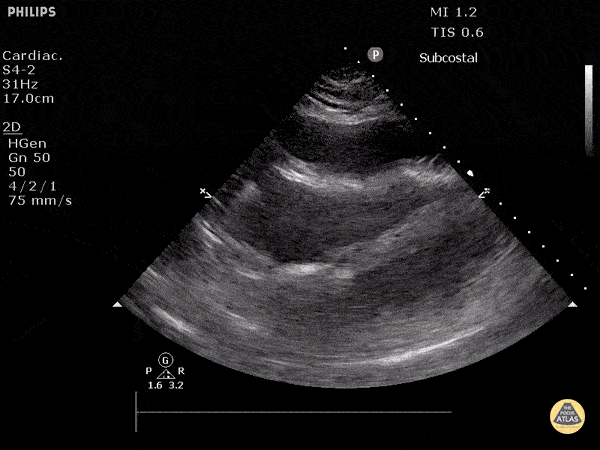

Subcostal View

• ANATOMIC LANDMARK: just below xiphoid

• Heart is ANTERIOR structure and mostly MIDLINE

• Probe flat, directed toward head, marker to the right

• Downward pressure

• SONOGRAPHIC LANDMARK: HEART

• Identify: LV, RV, LA, RA, MV, TV

• Pericardium +/- Pericardial fluid